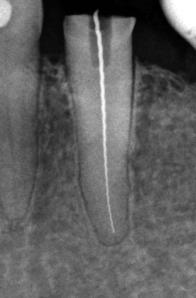

perfekte Wurzelkanalfüllung

Die dauerhafte Elimination der Bakterien aus dem Zahninneren wird durch die vollständige Erschließung der Wurzelkanäle, Reinigung und chemische Desinfektion sowie durch die abschließende sorgfältige Abdichtung des Wurzelkanals über seine gesamte Länge durch eine homogene wandständige Wurzelkanalfüllung erzielt. Wurzelkanalbehandlungen gehören zu den schwierigsten Disziplinen in der Zahnheilkunde. Neue Erkenntnisse, neue Techniken und neue Systeme eröffnen beste Voraussetzungen, mit denen man heute auch schwierige Wurzelkanalbehandlungen oftmals schonend, schmerzfrei und erfolgreich durchführen kann.